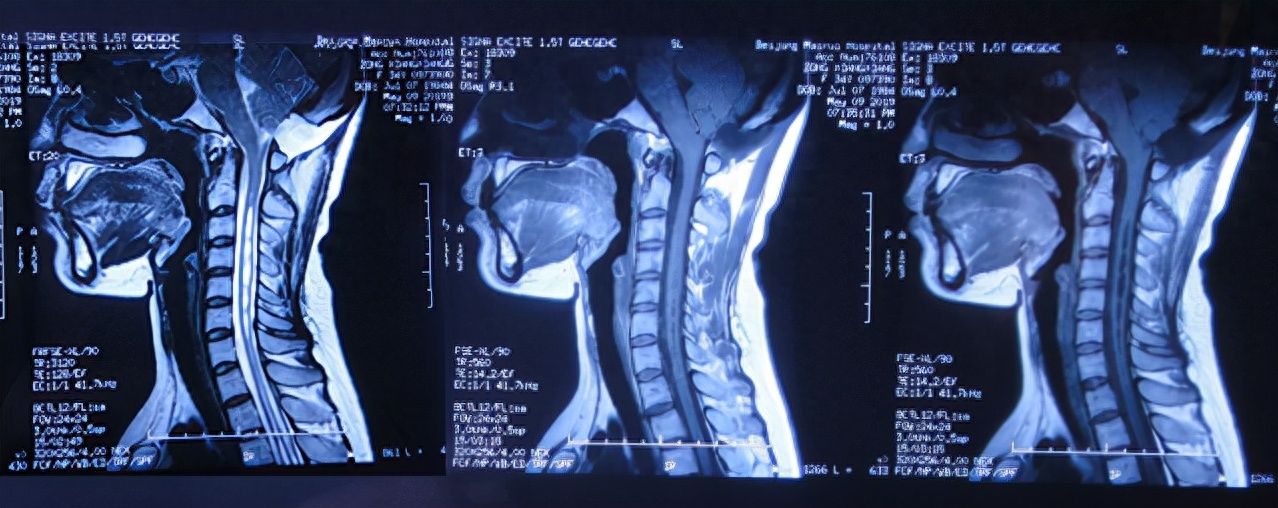

一、李小勇脑脊液科入院前病史

图-1:2019年2月10日头颅CT